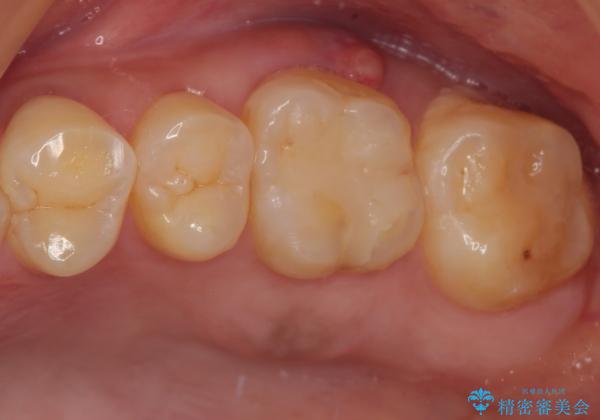

咬み合わせが非常に強く、臼歯のみに咬合力が集中している咬み合わせだったので、根管治療後はPGAクラウン(白金加金合金クラウン)にて補綴する治療計画となりました。

初回の根管治療を終えた2日後には膿の出口が消失し、咬んだときの不快な痛みもなくなりました。

PGAクラウンにしたことで咬み心地に全く違和感がなく、気にされていた審美面も、奥歯でありそれほど目立たないこともありますが、白金加金の色を気に入っていただけたので、患者様には大変満足していただけました。